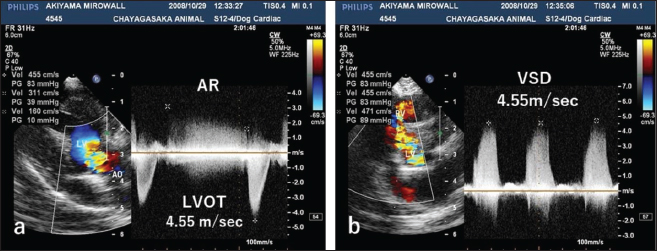

Fig. 4. CWD echocardiography after surgery. (a) Five days after surgery, the systolic pressure gradient (ΔP) between the LV and aorta (AO) had decreased from 83 mmHg (the preoperative value) to 40 mm Hg. The corresponding values for left ventricular outflow tract (LVOT) velocity were 4.55 and 3.17 m/seconds, respectively. (b) Thereafter, the values were essentially unchanged and were 48.7 mmHg (ΔP) and 3.49 m/seconds (LVOT) at 8.5 months.

The dog was monitored daily with physical examinations, including echocardiography, and the postoperative course was good. However, the dog remained in our hospital for 10 days until discharge to accommodate the owner, who lived remotely. Postoperative auscultation revealed a persistent grade 2/6 systolic murmur, and colour Doppler echocardiography revealed slight residual shunt blood flow through the VSD. As shown via thoracic radiography, the CTR was lower after surgery (66% at 10 days and 65.9% at 8.5 months) than before surgery (70%). As shown via CWD echocardiography, the systolic ΔP between the LV and aorta was also lower after surgery (40 mmHg at 5 days) than before surgery (83 mmHg) (Fig. 4a); after 5 days, it remained essentially unchanged and was 48.7 mmHg at 8.5 months (Fig. 4b). At 8.5 months, the dog had no clinical signs of heart disease and her body weight had increased to 3.9 kg. According to the referral hospital, the dog had no cardiac complications during the next 11 years.

In our study, CWD echocardiography was especially useful for monitoring blood flow velocity by calculating ΔP before and after surgery. As determined using this modality, the systolic ΔP between the LV and aorta was 83 mmHg immediately before surgery. According to the referral hospital, it was 50.7 mmHg 2 months before surgery. This slow increase in the ΔP presumably reflected the slow growth of the tumour, which was likely benign (Han et al., 2012). Five days after surgery, the ΔP had decreased to 40 mmHg (Fig. 4a), with little change over the next 8.5 months (Fig. 4b). Although echocardiography may indicate whether a tumour is benign or malignant, biopsy is required for definitive diagnosis of a cardiac myxoma.